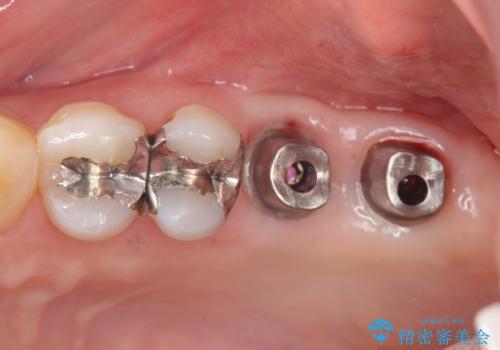

上顎奥歯のインプラント治療

- 88万円(インプラント×2・チタンカスタムアバットメント×2・ジルコニアクラウン×2・仮歯×2)費用は治療当時の料金となります

しっかりと食事ができるようになり、当院のインプラント治療に満足いただくことができました。